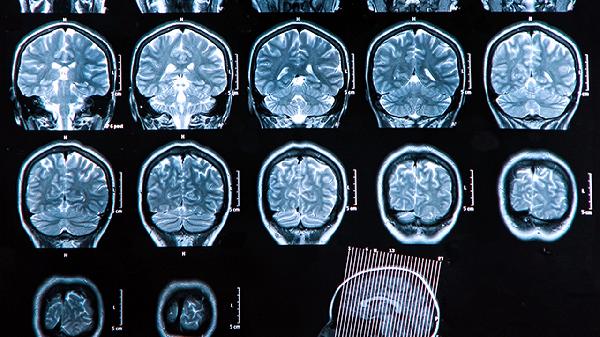

脑血栓常导致对侧肢体突发无力或瘫痪,表现为单侧手臂抬举困难、下肢拖行。这与大脑运动皮层或皮质脊髓束缺血有关,可能伴随肌张力增高或腱反射亢进。若基底节区梗死可能出现偏瘫伴感觉障碍。需紧急进行头颅CT或MRI检查明确梗死灶。

后循环血栓影响小脑或脑干前庭神经核时,会出现剧烈眩晕、平衡障碍及喷射性呕吐,可能伴随眼震或复视。椎基底动脉系统梗死还可导致饮水呛咳、吞咽困难等延髓症状。此类症状易误诊为耳石症,需通过DWI-MRI明确后循环缺血灶。